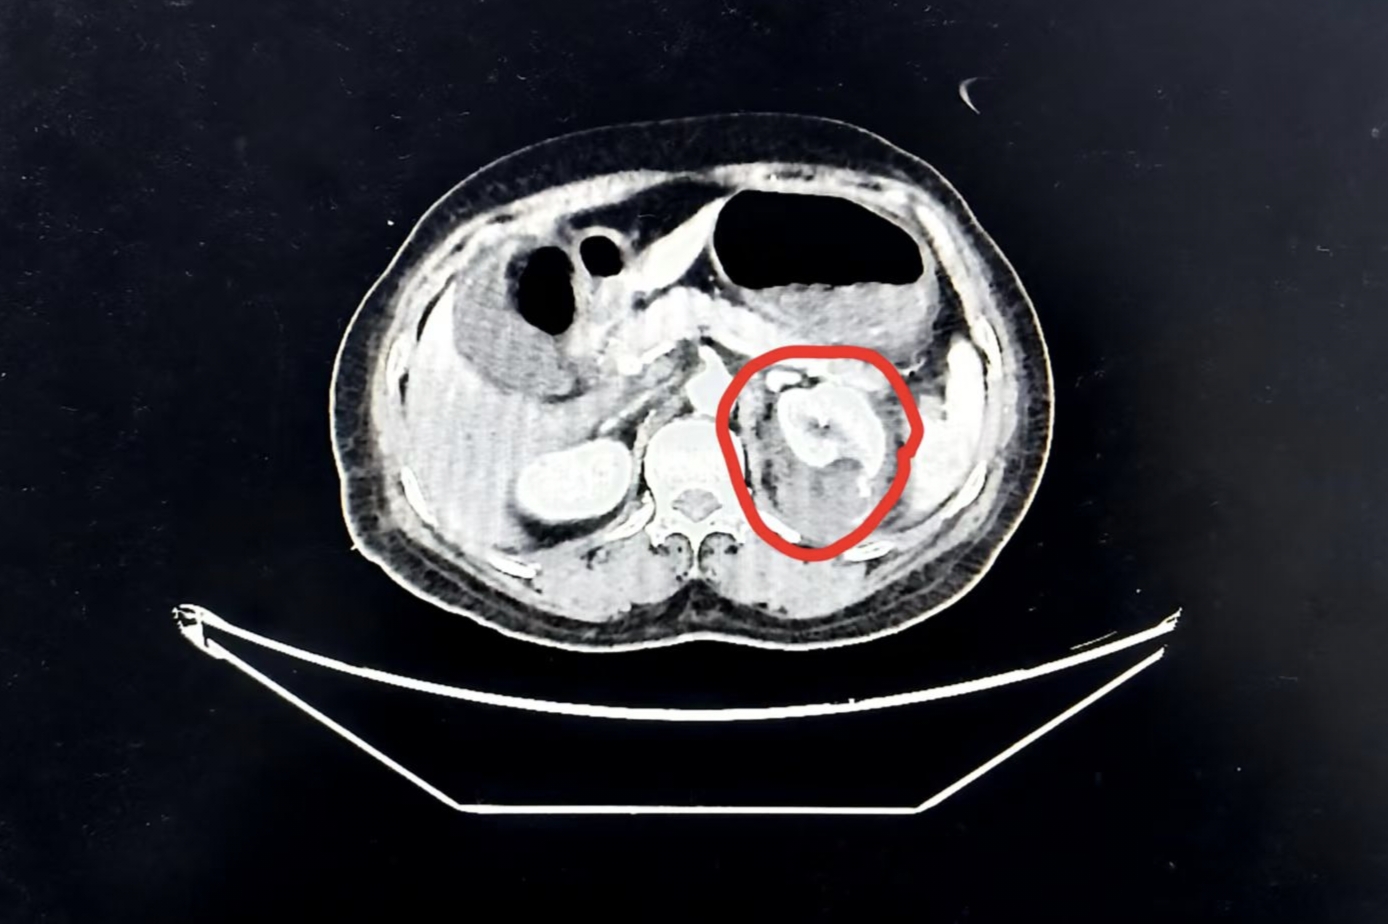

患者毛奶奶在车祸后的5个多小时被紧急送入医院ICU。入院时,她已出现失血性休克,伴随多发肋骨骨折、血胸、脑挫伤、肺挫伤等症状,生命体征极不稳定。ICU团队当即打响生命保卫“第一枪”,迅速开展高级生命支持,紧急实施气管插管、呼吸机辅助通气、抗休克、循环稳定维持等一系列抢救措施,为后续专科诊疗赢得了关键时间和稳定内环境。增强CT检查进一步显示,患者左肾周存在活动性出血,若不及时处置,不仅可能丧失肾功能,更会危及生命。

左肾破裂